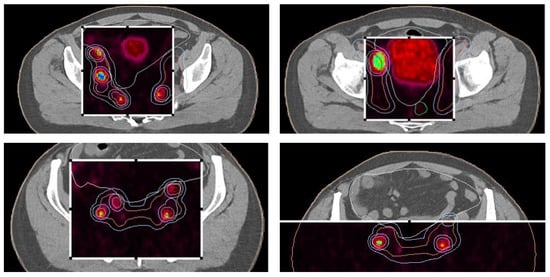

During the planning phase of the radiotherapy treatment course, a PET/CT scan was performed to delineate the metastatic sites accurately and guide radiotherapy planning. The radiotherapy regimen included teleradiotherapy targeting the prostate and affected lymph nodes with radical intent, utilizing a simultaneous integrated boost (SIB) approach with 45 Gy/60 Gy delivered in 25 fractions (Figure 2). Additionally, a high-dose–rate (HDR) brachytherapy boost of 15 Gy was administered in a single fraction to the prostate to achieve maximum local control (Figure 3).

Figure 2. Radiotherapy treatment planning—SIB 45 Gy/60 Gy/25 fx. The treatment plan is visualized across axial, coronal, and sagittal planes, with a corresponding dose–volume histogram illustrating the spatial distribution of radiation doses and treatment field coverage. The color spectrum represents different dose levels, with red indicating the highest dose areas and blue indicating the lowest dose areas. The plan was designed to maximize tumor coverage while sparing healthy tissue.